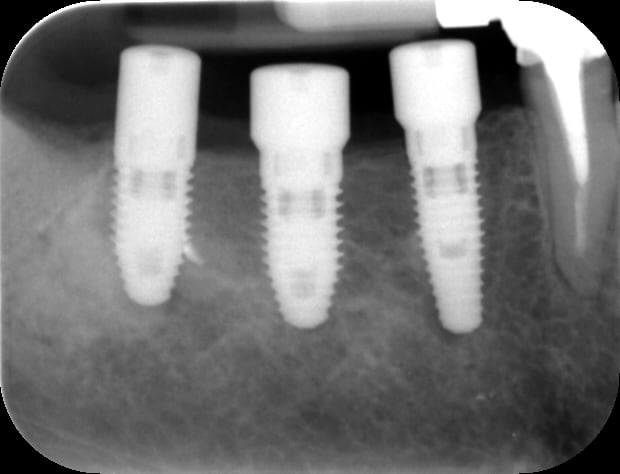

Et voilà l'objet du délit

3dslice1 2011 05 17 20 03 31 ohbadz - Eugenol

bein aux vues de tes images...si, tu as du taper la corticale linguale...

Je pense aussi que l'apex des implants est dans la corticale linguale

Mais pourquoi diable avoir mis une vis de cica WP 5x5 en 47 et pas une 6x5 comme en 46 ?

Pour ce qui est du dernier en 47 mon cher chicot tu as l'oeil... Moi je devais dormir à la fin de l'intervention car c'est seulement en prenant le cliché que je me suis rendu compte que j'avais pris un 5 mm. Du coup je l'ai immédiatement dévissé pour mettre un 6mm. ;+))